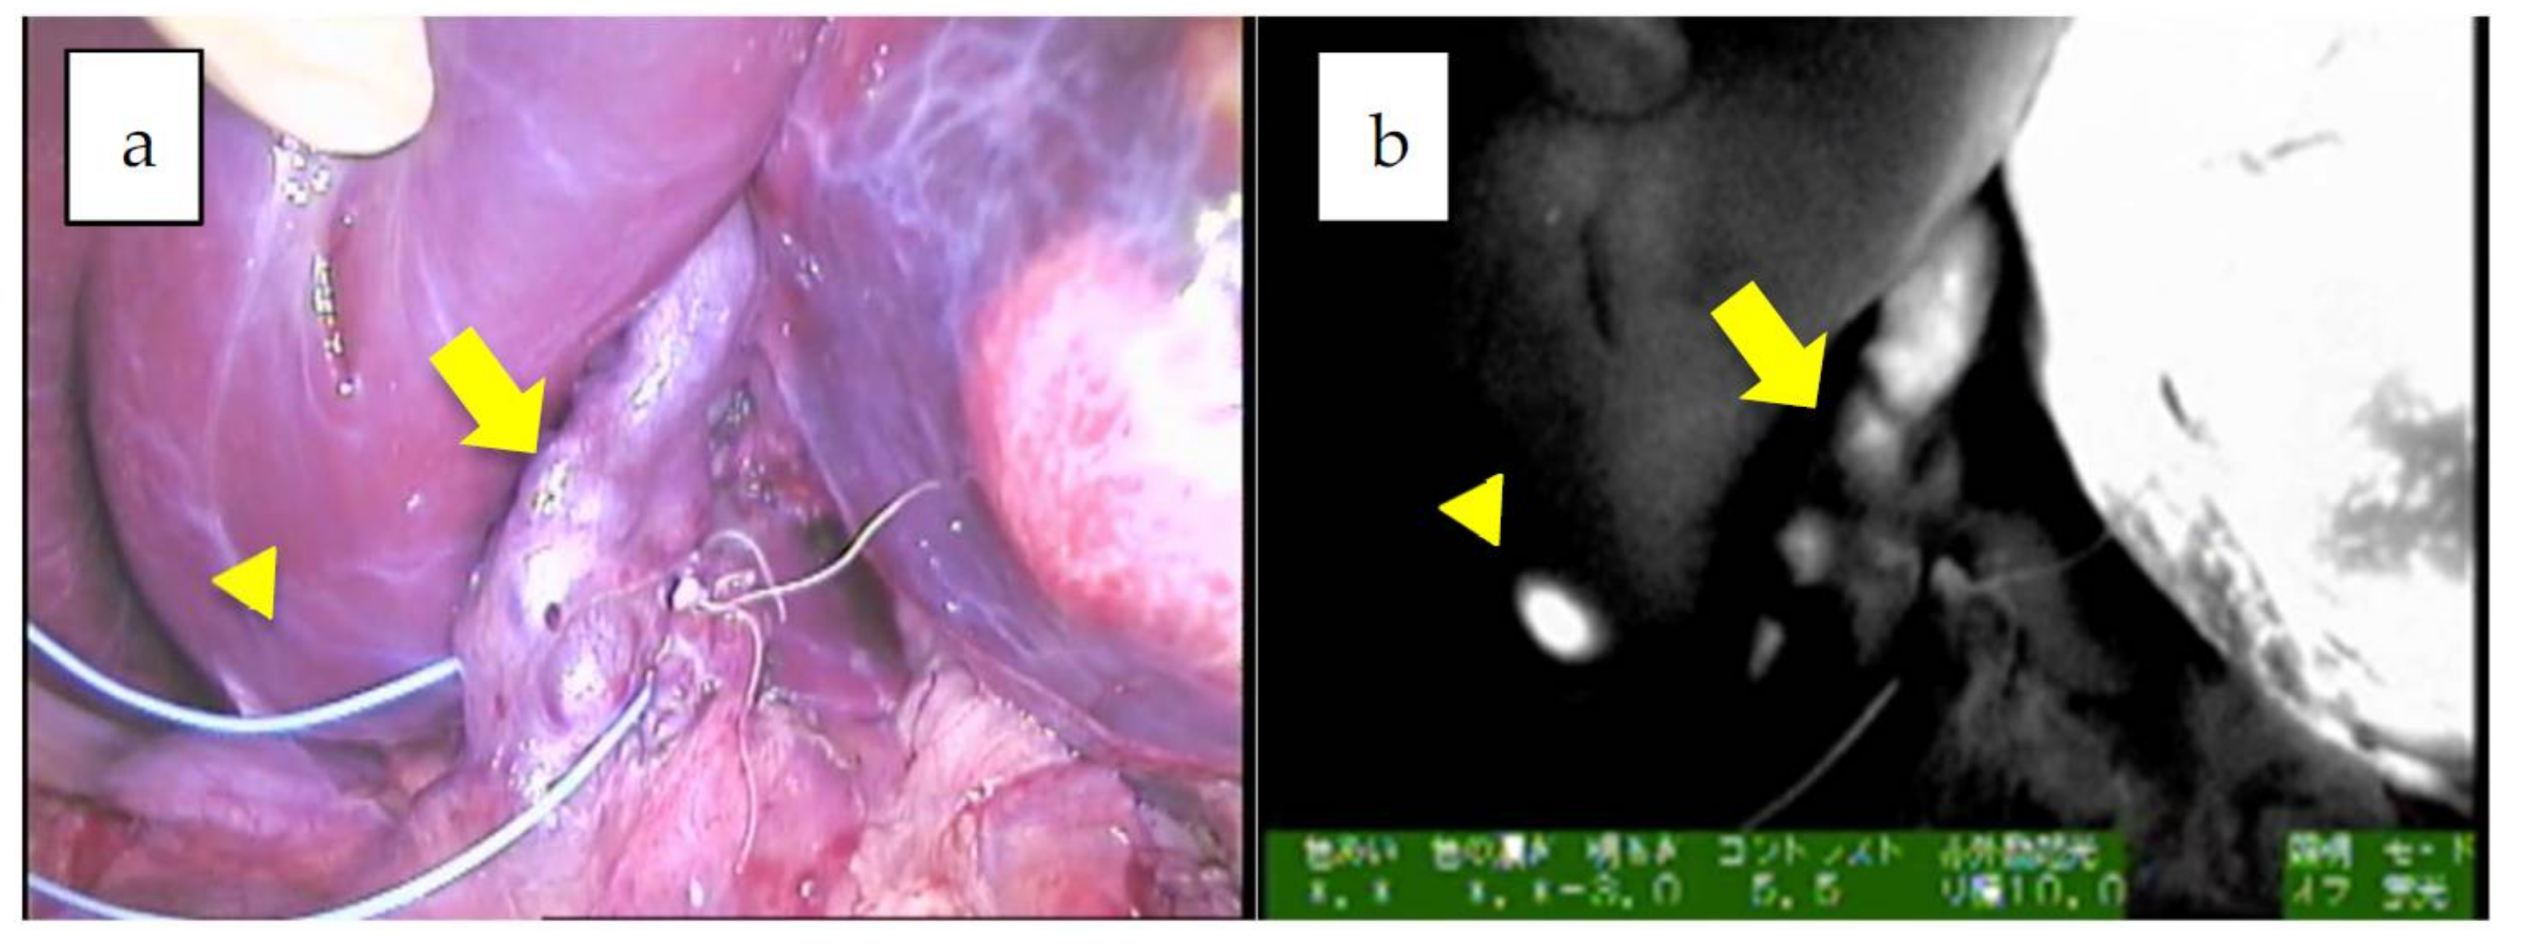

Figure 2.

a,b: The hilum of the liver in Patient 12. A giant tumor with uneven fluorescence in the left lobe along with intrahepatic metastasis (diffuse pattern) is indicated by an arrowhead. Of note, the common bile duct is also visualized, presumably due to residual fluorescence, indicated by an arrow (mixed epithelial and mesenchymal, post-chemotherapy).